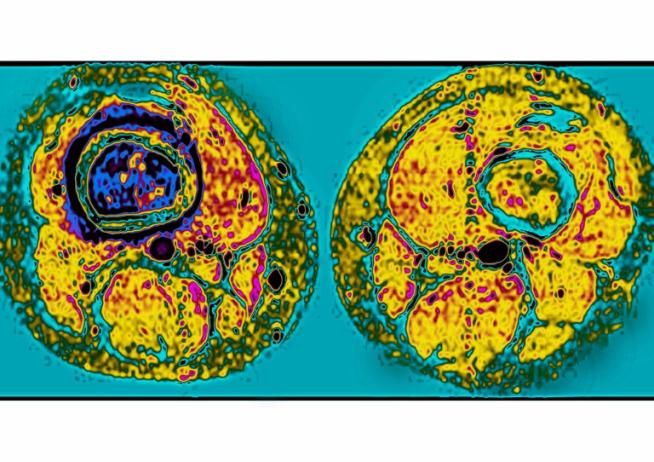

Tumore ossa, protesi ad anca fa fare i primi passi a bimba di 17 mesi